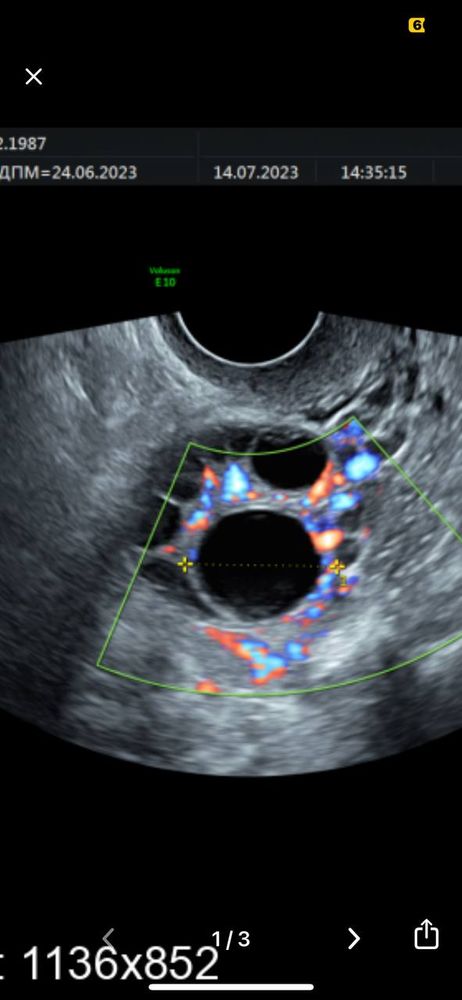

Добрый день, такой вопрос может у кого-то было такое, 14 дней назад сделала Лапароскопию (делали насечки) в связи с бесплодие, сегодня 14 день цикла, ждала овуляцию, но она как мне сегодня сказали была 3 дня назад, что вот жёлтое тело 2.5 на 2.2 см, на фото выше, что увы и ах прозивали, дак я вот теперь и думаю может ЖТ перепутали с ДФ, как-то рано она пришла, врач УЗИ сказала что это точно ЖТ так как кровоток есть ( на фото с лева 2 белые точки)

Они совершенно по разному на узи. У жт хорошо видно кровоток. Его смотрят как-то разноцветно, хорошо видно. И показывают. А еще жидкость в брюшной полости должна быть. ДФ это полностью черный круг без кровотока (жидкость поглощает уф лучи и выглядит черным цветом)

Валерия , вот мне тут сказали, что это жт, а на самом деле это был дф, по размерам 21 мм

Вот так выглядит желтое тело